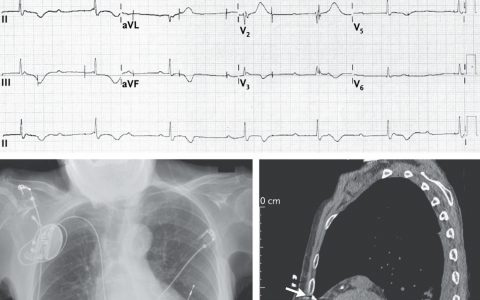

1970年首次描述了在不使用x线透视的情况下插入肺动脉导管(PAC)。它具有多个端口,可测量心内压和热稀释心输出量、药物输注以及心房或心室起搏。导管可在ICU床旁放置,无需通过大口径中心静脉导入器透视。当导管穿过上腔静脉、右心房和右心室进入肺动脉时,可以使用特征性波形识别PAC的位置。下图显示了PAC穿过心脏结构时的波形。

右心房、心室、肺动脉或肺动脉闭塞压(也称为肺毛细血管楔压)与左心室压之间的相关性较差,因此,这些测量值充其量可以被视为替代指标。胸内和心包压力的波动也会对楔形压力测量的实用性产生负面影响,因为左心室充盈压是跨心室壁跨壁压力的真实测量值。PAC在肺动脉高压管理中仍具有重要作用,包括诊断和监测治疗反应。